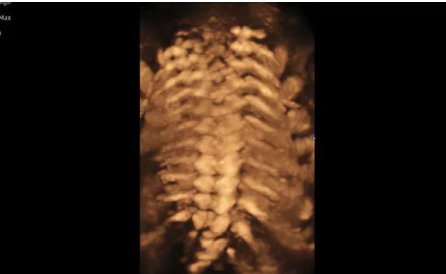

Hera i 10繼承并升級了全球首款5D超聲“三星麥迪遜WS80A”的“晶體結(jié)構(gòu)”成像理念,即將CrystalBeam?波束形成技術(shù)、CrystalLive?超聲成像引擎、S-Vue Transducer?視覺傳感器集于一身,提供更清晰的圖像。

3D/4D成像方面,Hera i 10通過結(jié)合先進(jìn)的圖像渲染技術(shù),著重加強(qiáng)了邊緣和小結(jié)構(gòu)的可視化能力。